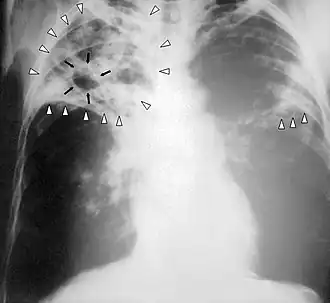

Chest X-ray of a person with advanced tuberculosis

Chest X-ray of a person with advanced tuberculosis: Infection in both lungs is marked by white arrow-heads, and the formation of a cavity is marked by black arrows.

Chest radiograph

In active pulmonary TB, infiltrates (opaque areas) or scarring are visible in the lungs on a chest X-ray. Infiltrates are suggestive but not necessarily diagnostic of TB. Other lung diseases can mimic the appearance of TB; and this test will not detect extrapulmonary infection or a recent infection.[109]